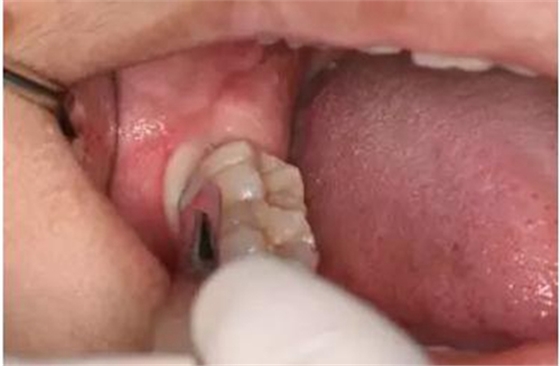

圖6. 從37頰側(cè)中份齦溝內(nèi)開始切開,向磨牙后區(qū)延伸

圖7.切開47遠(yuǎn)中齦溝并延長(zhǎng)至磨牙后區(qū)約1cm。

圖8.形成一個(gè)只有水平切口的小袋形口